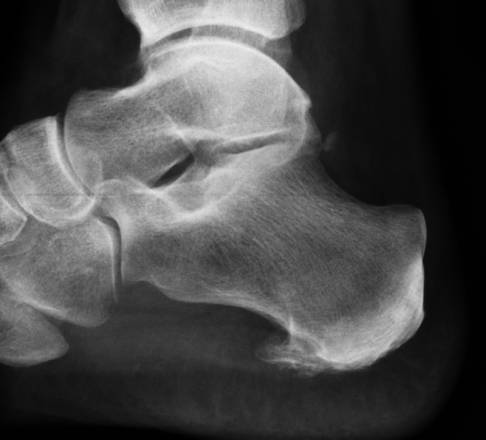

Der untere Fersensporn hat seinen Namen von dem im Röntgenbild häufig gut sichtbaren knöchernen Anbau am Plantarsehnenansatz im unteren Bereich des Fersenbeins. Man spricht auch von einem plantaren Fersensporn.

Kalkablagerungen in der Plantarsehne bilden den im Röntgenbild oft deutlich sichtbaren unteren Fersensporn. Dieser kann zusätzlich das Bindegewebe belasten. Durch den anhaltenden Druck der Kalkeinlagerung kommt es in der Umgebung des Fersensporns zu einer verstärkten schmerzhaften Entzündung. Deshalb kann in wenigen Fällen die Entfernung des Kalksporns durch eine endoskopische Operation (Fersenspornabtragung) ein Weg sein, die Schmerzen des Patienten zu behandeln.

Nach der klinischen Untersuchung des Fersensporns kommen verschiedene bildgebende Verfahren zum Einsatz. Das Röntgenbild zeigt eine mögliche Fehlstellung oder Fehlbelastung der schmerzenden Ferse. Länge und Form des Fersenbeins sind wichtige Aussagen der Röntgenuntersuchung. Zusätzlich können Röntgenbilder im Stehen durchgeführt werden und über belastungsabhängige Fehlstellungen Aufschluss geben.